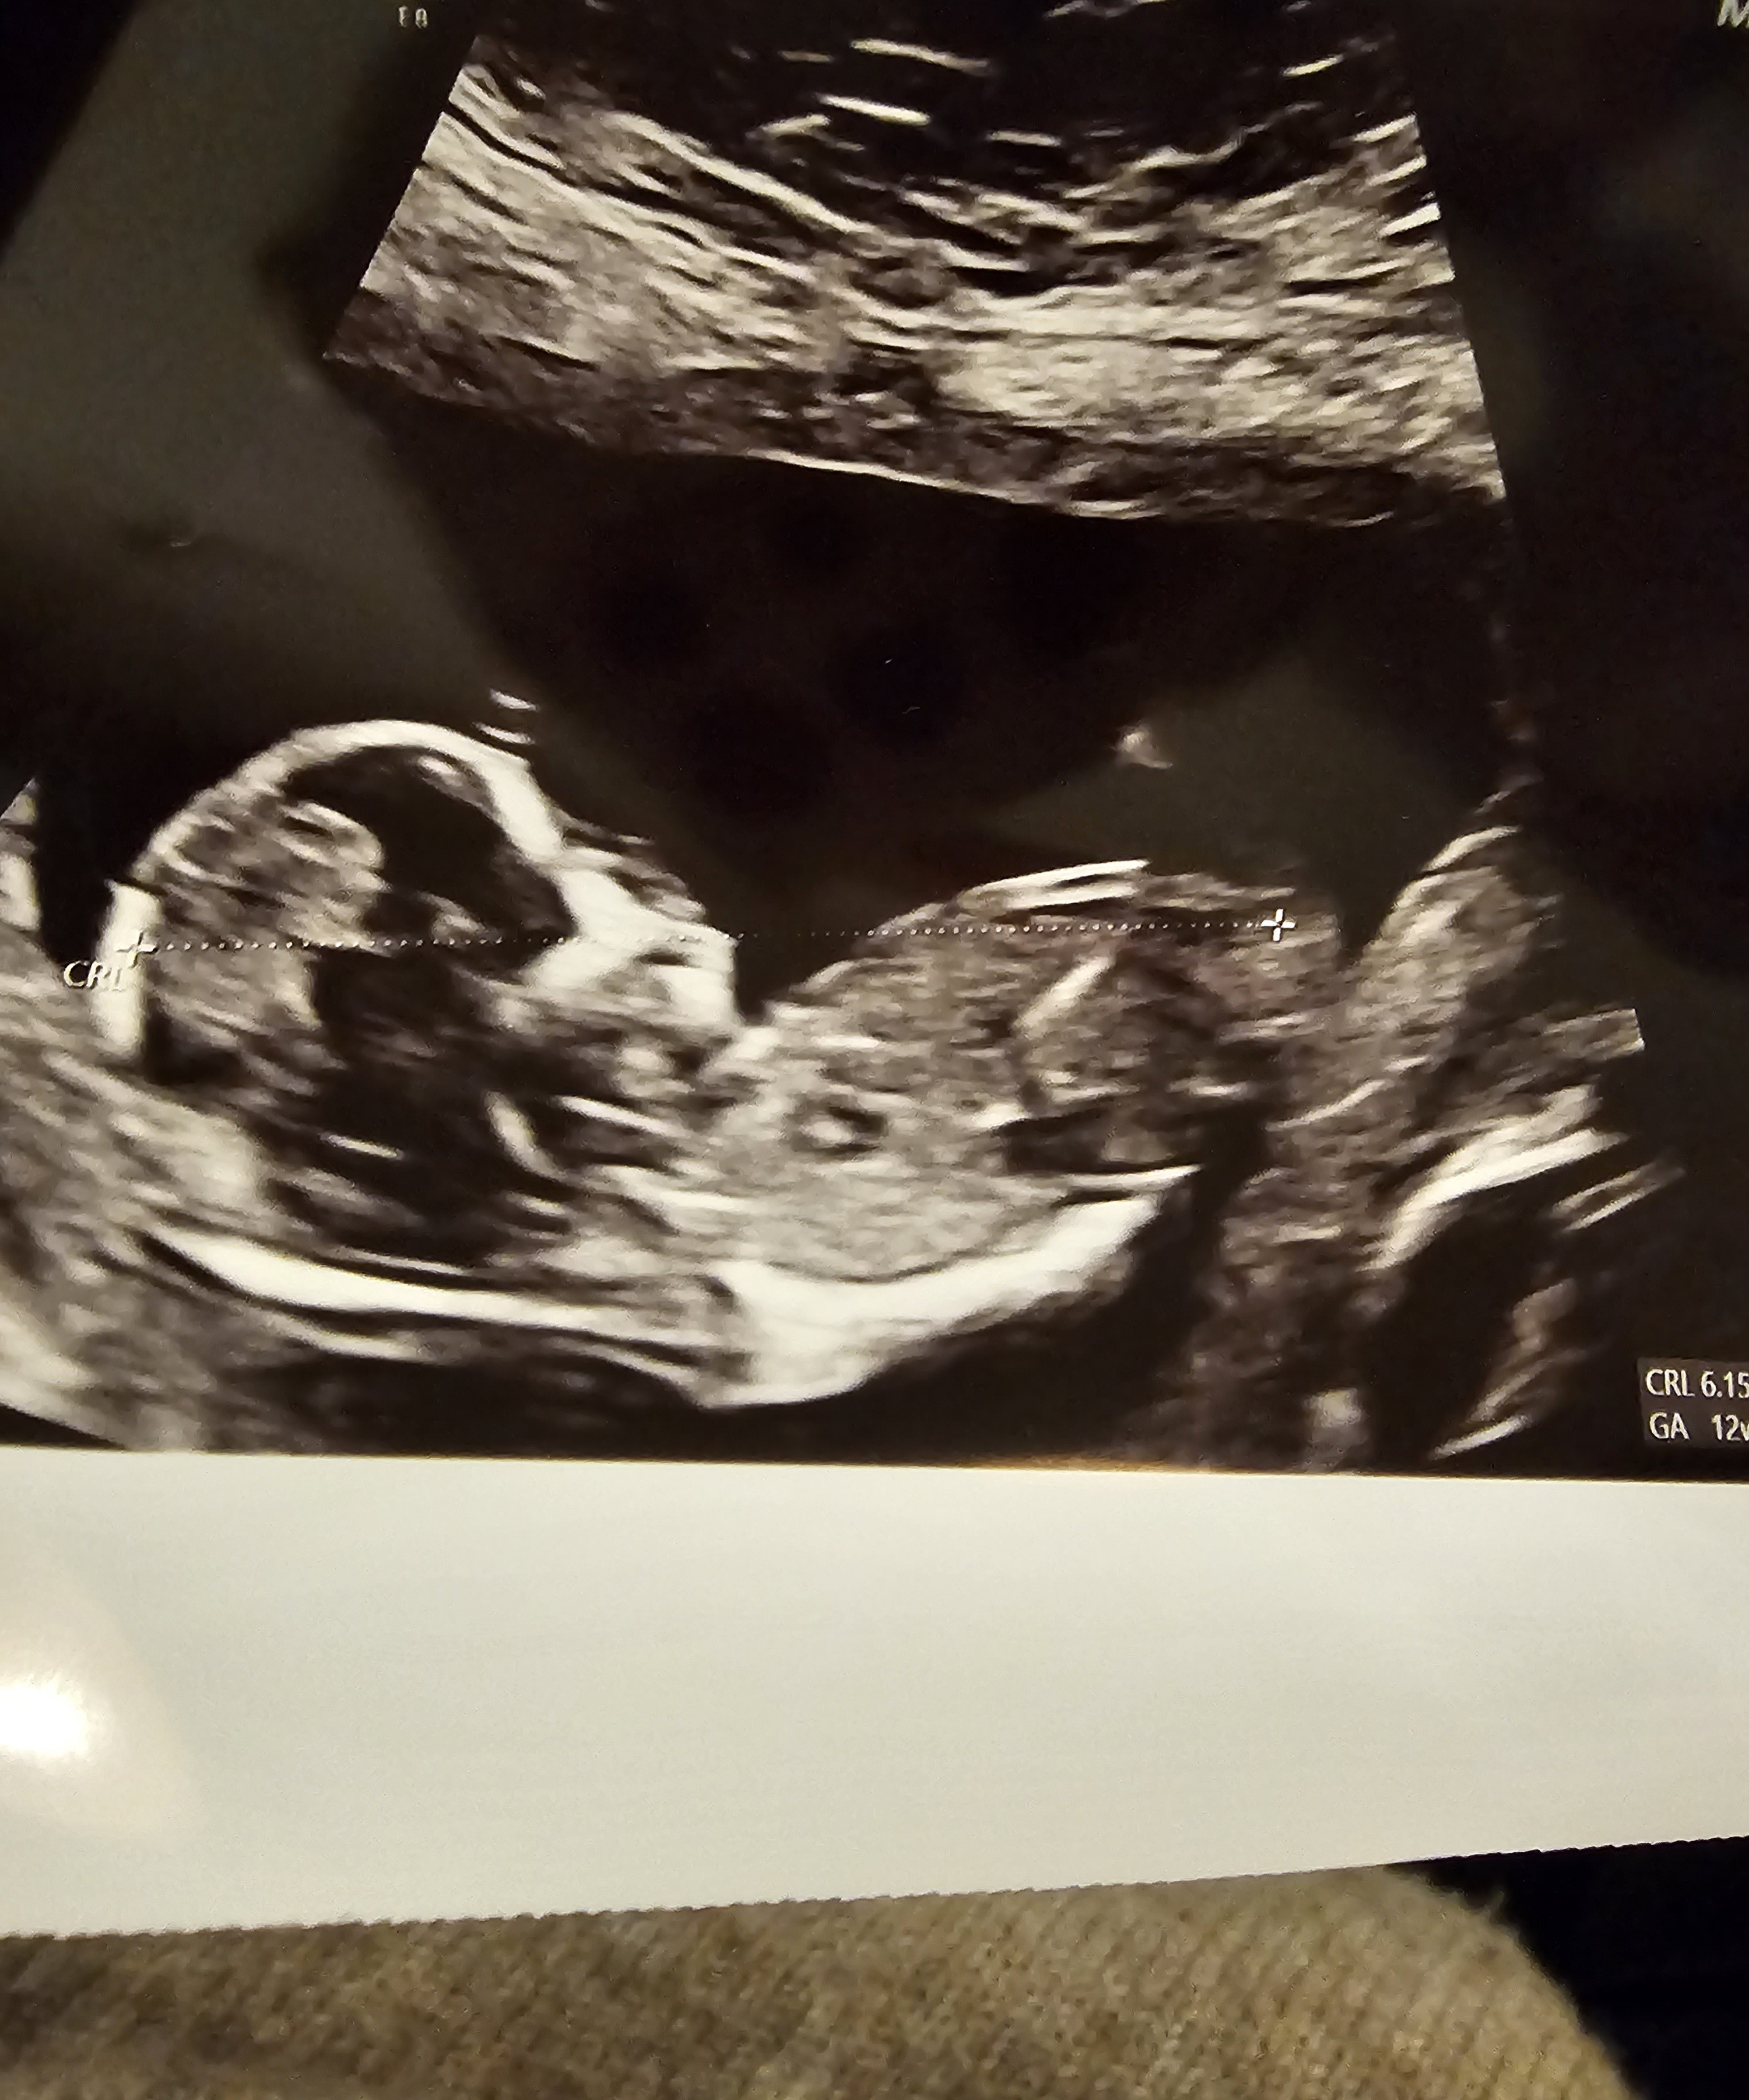

Hej kochane. Czy ktoś zagląda tutaj? I mógłby coś powiedzieć wg tych zdjęć 🙂

• 20241112_174040.jpg

20241112_174040.jpg

953,5 KB · Wyświetleń: 310

• 20241112_174014.jpg

20241112_174014.jpg

904,6 KB · Wyświetleń: 297

• 20241112_174011.jpg

20241112_174011.jpg

1,4 MB · Wyświetleń: 288